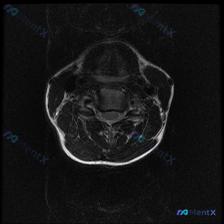

分享一张颈椎MRI T2轴位片,整理了完整的读片和分析思路,大家一起讨论看看。 病例基本影像信息 这是一张颈椎椎间盘水平的T2加权轴位图像,图像对比度良好,脑脊液呈高信号,脊髓中等信号,椎间盘中低信号,没有明显严重伪影,解剖层次清晰。 系统观察各个结构: 1. 骨骼关节:椎体形态完整,椎体后缘可见轻...

刚整理了一份很有启发的颈椎MRI读片病例,核心问题是“这张图里能观察到椎间盘病变吗?”,把完整分析思路分享给大家。 影像基本信息 这是一张颈椎MRI轴位T2加权图像,我们先把观察到的结构特征理清楚: 1. 椎体与椎管:脑脊液呈高信号,脊髓居中,形态规整,内部没有明显异常信号(无水肿灶);椎体后缘有轻...

整理了这张颈椎MRI读片病例和完整分析思路,分享给大家一起讨论 病例与影像基础信息 本次读片对象为颈椎MRI-T2序列轴位单张影像,核心问题是观察图像是否存在椎间盘病变: 1. 影像质量良好,对比度清晰,脊髓、脑脊液、软组织结构显示清楚,无明显运动伪影,扫描层面为颈椎中下段水平 2. 核心影像表现:...

刚看到一个有意思的读片病例,用户提供了一张颈椎MRI-T2序列轴位图像,明确提问是围绕「椎间盘病变」的观察,整理一下完整分析思路分享给大家。 一、影像基本信息 这是颈椎中下段的MRI-T2加权轴位图像,我们先按层次梳理客观观察结果: 1. 椎管与脊髓:脊髓位于椎管中央,形态规则,内部信号没有异常高/...